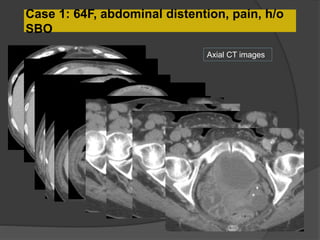

Case 1: 64F, abdominal distention, pain, h/o

SBO

Axial CT images

• Multilobulated thick-walled cystic lesion in the lesser sac and extending along the

adjacent peritoneal spaces and gastrohepatic ligament. Cystic lesion in the left

hemipelvis

• Minimal ascites, omental and mesenteric thickening

Present exam 15 days ago

Increased size

15 days

ago

Present exam

Case 1 Diagnosis: Recurrent metastatic disease

with mucinous ovarian tumor